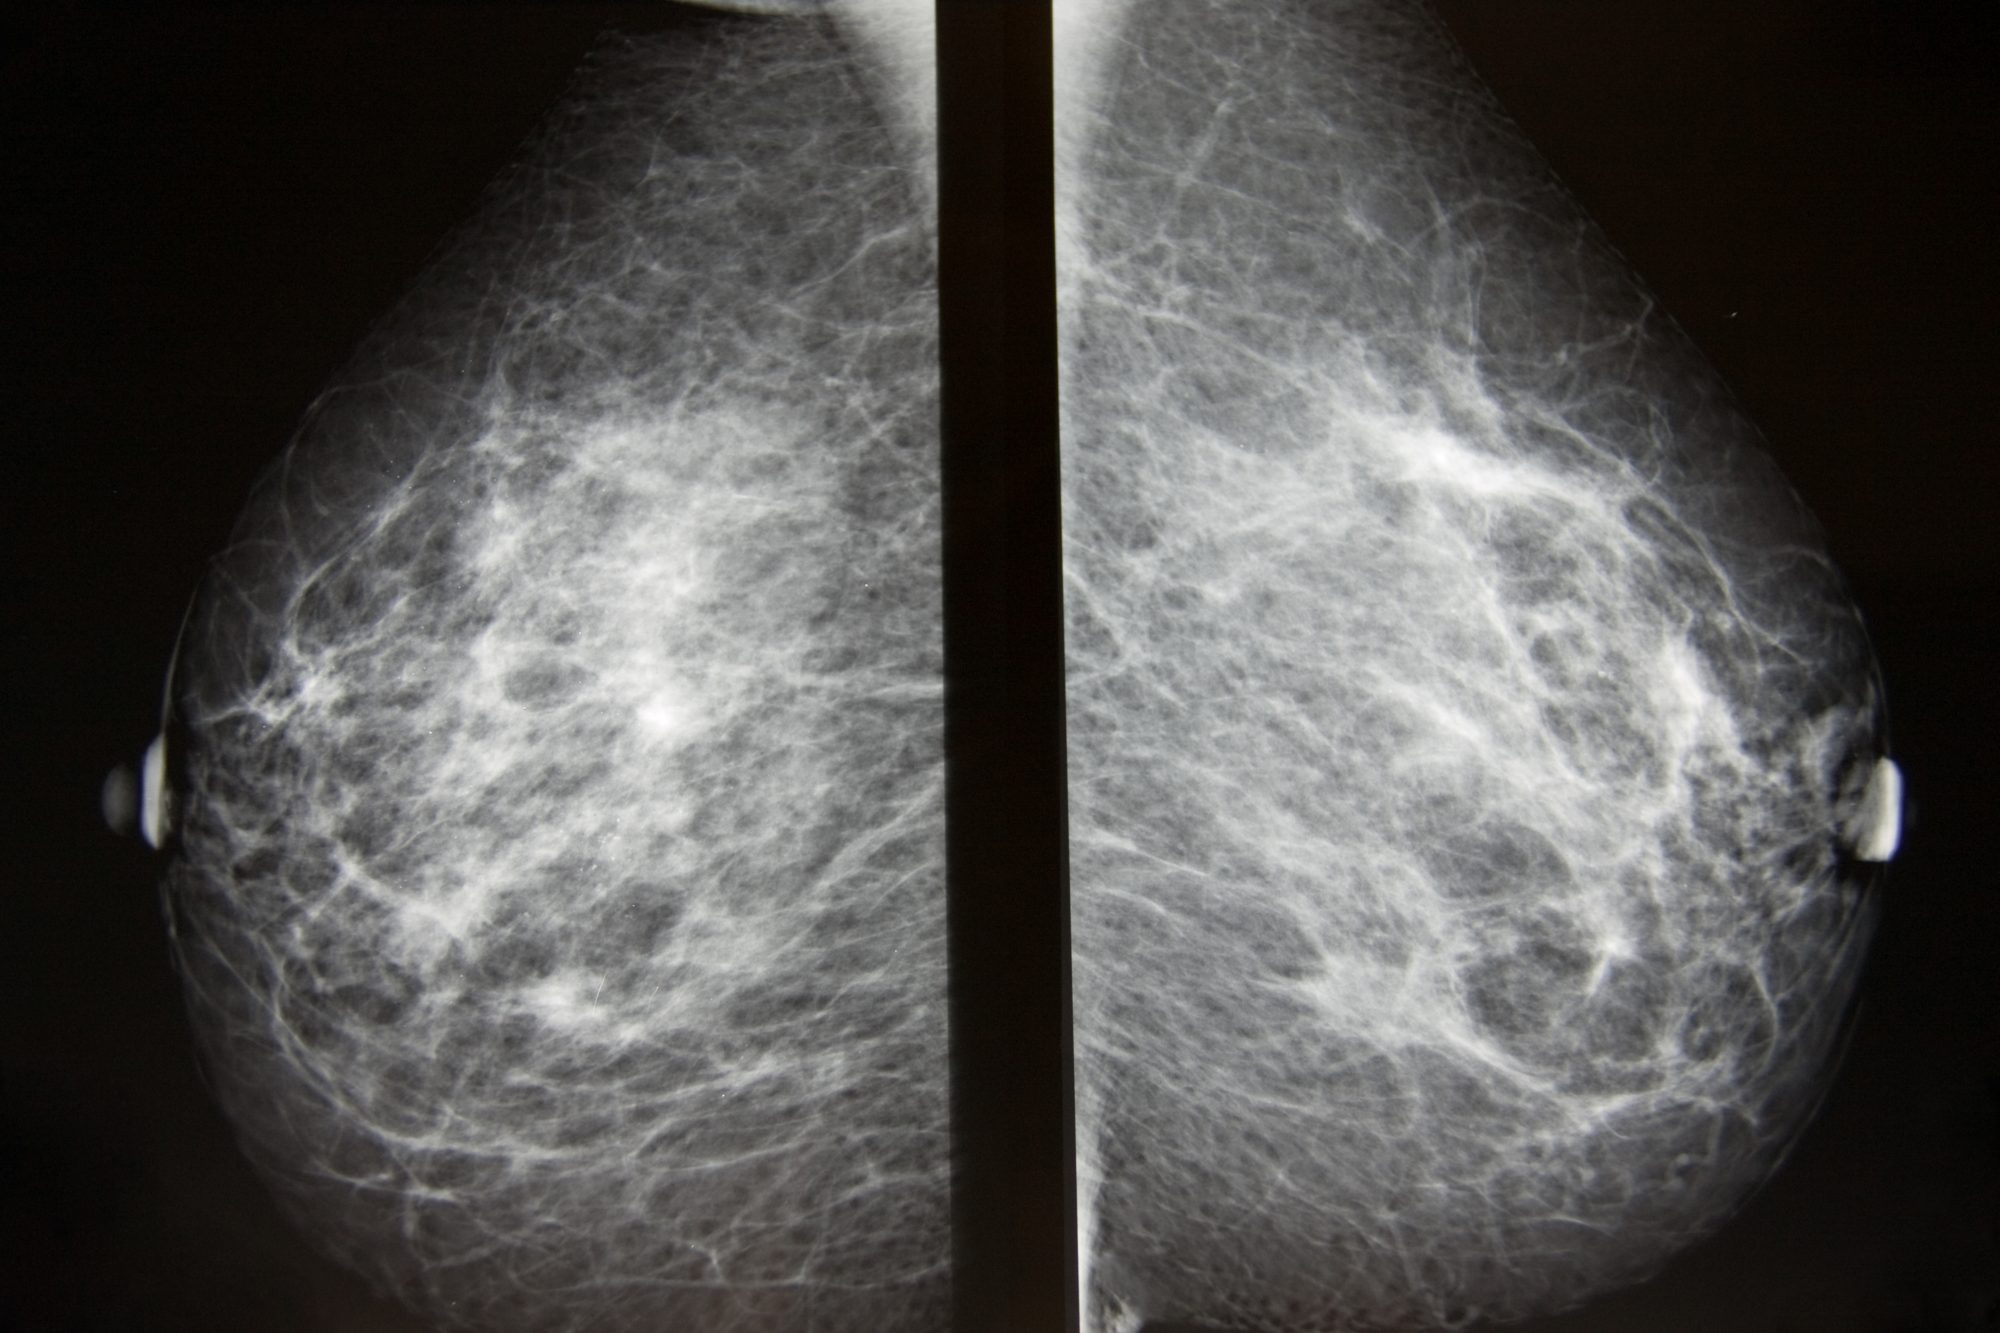

Что такое маммография: важность, процесс и результаты